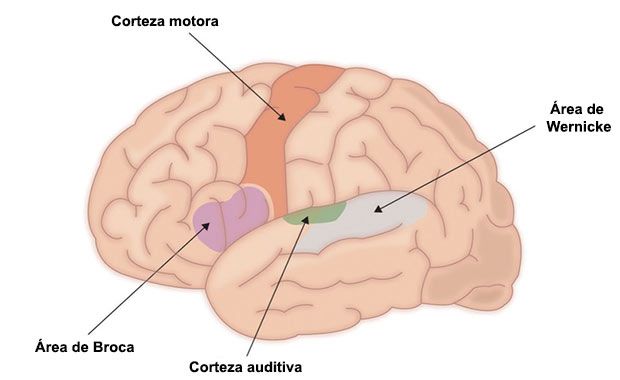

El área de Broca ubicada en la tercera circunvolución frontal (en el lóbulo frontal) del hemisferio cerebral izquierdo, si bien en algunos casos excepcionales se encuentra en el hemisferio derecho. Concretamente, según el mapa de Brodmann, ocupa las áreas 44 y 45 de Brodmann, cerca del ojo y pegado a la parte frontal del lóbulo temporal.

Este síndrome se distingue especialmente de otro tipo de afasia relacionada con una parte del cerebro llamada área de Wernicke. Se trata de la afasia de Wernicke, en la que, en comparación a la afasia de Broca, el lenguaje y la escritura son mucho más fluidos, pero se pierde la capacidad de dotar de significado a lo que se dice o a lo que se lee o escucha, por lo cual no se entiende lo que dicen otros.